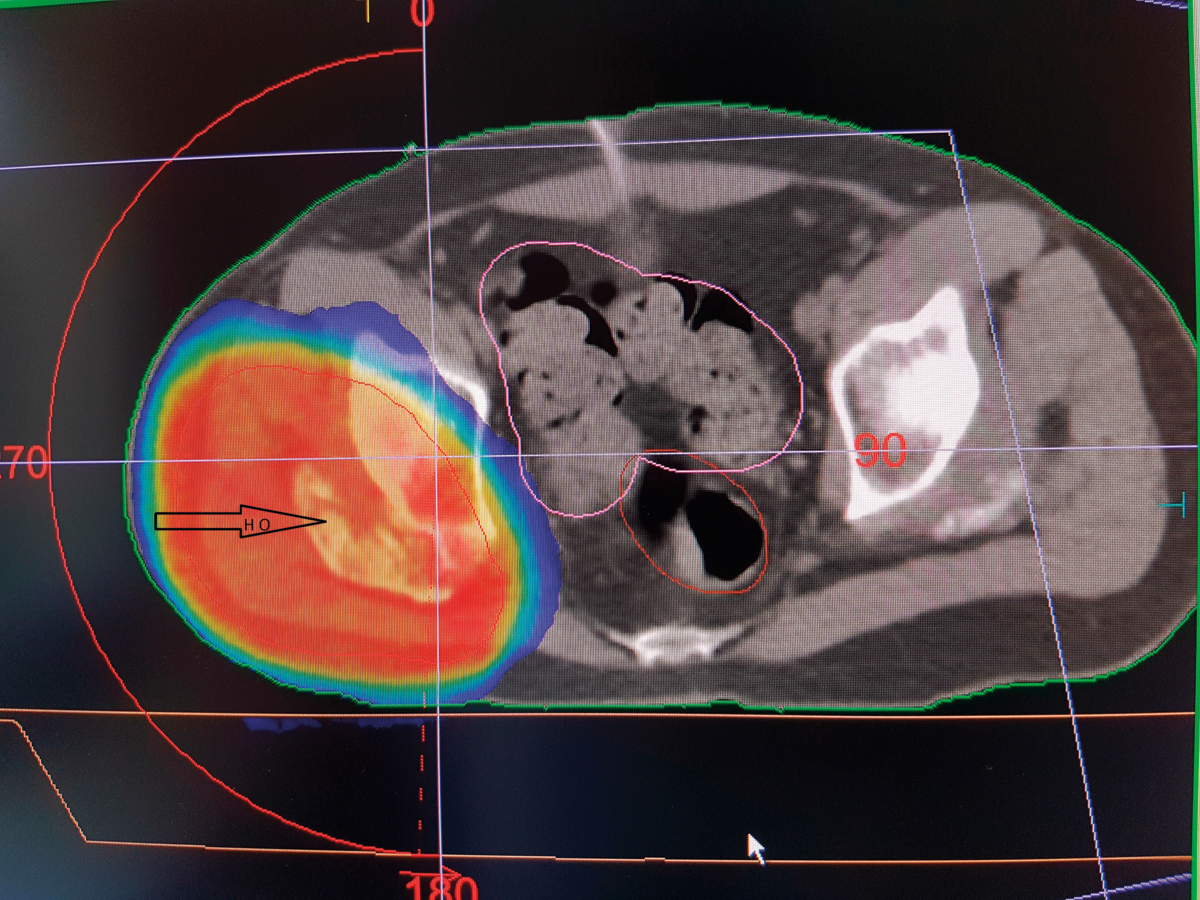

Die volumenmodulierte Strahlentherapie einer heterotropen Ossifikation am rechten Hüftgelenk stellt keine größere Belastung für die Beckenorgane dar. Die volumenmodulierte Strahlentherapie einer heterotropen Ossifikation am rechten Hüftgelenk stellt keine größere Belastung für die Beckenorgane dar. © Schneider T, Schneider­ K. internistische praxis 2019; 61: 284-300 © Medien­gruppe Oberfranken - Fachverlage GmbH & Co. KG, Kulmbach

Bei Hämangiomen kommt die Strahlentherapie meist in Einzeldosen von 2 Gy mit einer mittleren Gesamtdosis von 30–40 Gy zum Einsatz, was keinesfalls einer klassischen Niedrigdosis entspricht. Für rezidivierende oder inoperable aneurysmale Knochenzysten bietet sie mit 26–30 Gy eine Option. Bei heterotroper Ossifikation können zur Prophylaxe bei über 50-Jährigen statt NSAR verschiedene Bestrahlungsschemata genutzt werden: präoperativ oder postoperativ einmalig bzw. mehrfach. Erzielt eine einzelne Variante nicht ausreichend Effekte, lassen sich für Hochrisikopatienten Radiatio und NSAR kombinieren. Für das Patellaspitzensyndrom liegt hingegen keine Evidenz vor, die Hamburger Kollegen haben laut eigenen Erfahrungen bislang nur moderate Effekte erzielt.